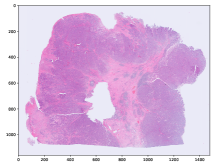

Refer to caption

(a) MSI negative

(b) MSI positive

(c) MSI negative

Figure 3: Three examples of diagnostic slides from the CancerScout Colon dataset. Slides are plotted with an optical magnification of 2.5.

2.1 The CancerScout Colon Data

For this study, we use 208520852085 diagnostic slides from 840840840 colon cancer patients. We have estimated the MSI status of all patients using clinic immunohistochemistry (IHC) based test. A total of 144144144 (17 %times17percent17\text{\,}\mathrm{\char 37\relax}) patients in the cohort are MSI positive. In addition, we have annotated tumor regions in 299299299 slides from 279279279 patients, with the open-source annotation tool EXACT [18]. We use these annotations to train a segmentation model for our reference two-stage approach. Ethics approval has been granted by University Medical Center Goettingen (UMG).

2.1.2 Image Data

The images are magnified H&E stained histological images of formalin-fixed paraffin-embedded (FFPE) diagnostic slides. Images are scanned with an isometric resolution of 0.250.250.25 microns/pixel, which corresponds to a microscopic magnification of 40 ×times4040\text{\,}\times. For all patients, a new slide was freshly cut, stained, and digitalized for this study. Figure 3 shows examples of those slides, we call them cnew slides. For 725725725 patients we have digitalized cold slides. These are archived slides which were cut and stained when the patient was initially treated. Each of the slides is from the same FFPE block as the corresponding cnew, located in very close proximity (about 2 µmtimes2micrometer2\text{\,}\mathrm{\SIUnitSymbolMicro m}). Those slides are used to augment training but not for evaluation. For 274274274 patients we have collected hnew slides. These are slides which only contain healthy tissue taken from the resection margins of the FFPE block. For 246246246 patients we have collected hold slides. These are slides which were cut and stained when the patient was initially treated, located in close proximity (about 2 µmtimes2micrometer2\text{\,}\mathrm{\SIUnitSymbolMicro m}) to the corresponding hnew slide We use those slides to increase the training data for our segmentation model.